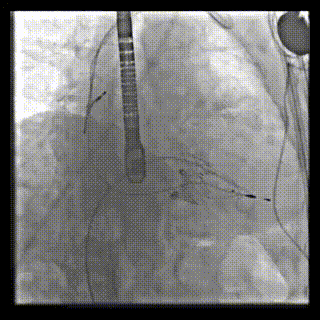

2021年12月24日,復(fù)旦大學(xué)附屬中山醫(yī)院葛均波院士團(tuán)隊(duì)成功應(yīng)用LuX-Valve Plus為一例極重度三尖瓣反流(TR)合并房顫、房缺的患者完成了經(jīng)血管三尖瓣置換術(shù),這是在前基礎(chǔ)上,本周完成的第三例經(jīng)血管三尖瓣置換手術(shù),葛均波院士、周達(dá)新教授等與心外科魏來教授、賴顥教授,心超室的潘翠珍教授、李偉教授及麻醉科的郭克芳教授共同完成了本周手術(shù),均獲得圓滿成功!患者術(shù)后超聲顯示無TR,臨床癥狀明顯改善。本周手術(shù)的成功也為LuX-Valve Plus救治性臨床研究添上了濃墨重彩的一筆。

本周三例接受LuX-Valve Plus經(jīng)血管三尖瓣置換術(shù)的患者中,第一例患者為冠狀動脈旁路移植術(shù)+Bentall+二尖瓣成形術(shù)后;第二例患者為永久起搏器植入術(shù)后,存在跨三尖瓣導(dǎo)線;第三例患者合并房顫、房缺及左心耳封堵術(shù)后。

三例患者入院后,葛均波院士團(tuán)隊(duì)周達(dá)新教授、潘文志教授、張?jiān)床┦?、陳莎莎博士及心超室的潘翠珍教授、李偉教授對患者的情況進(jìn)行詳細(xì)評估和討論,最終決定為三例患者選擇LuX-Valve Plus40mm、50mm和50mm型號的瓣膜進(jìn)行手術(shù)治療。手術(shù)后即刻拔除氣管插管,術(shù)后患者三尖瓣反流癥狀得到顯著改善,復(fù)查心超結(jié)果顯示人工三尖瓣瓣膜支架固定穩(wěn)定,瓣葉關(guān)閉形態(tài)未見異常,未見明顯反流。